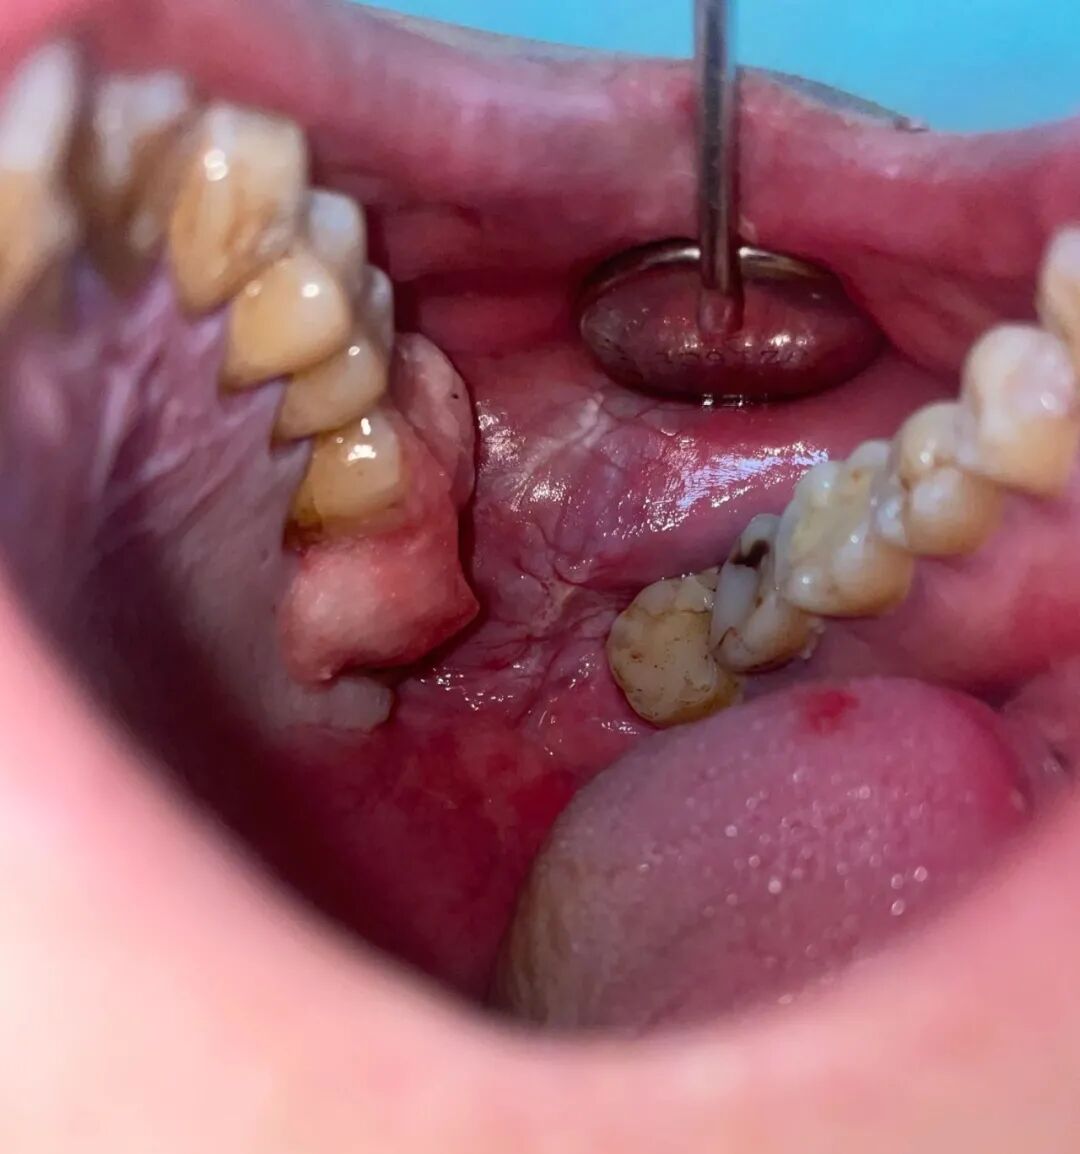

除了毒品屬性,檳榔里的化學(xué)物質(zhì)經(jīng)咀嚼后形成的亞硝基,是明確致癌的化合物。檳榔較硬,咀嚼時(shí)易對(duì)口腔黏膜造成機(jī)械創(chuàng)傷,導(dǎo)致口腔粘膜纖維化、牙齦炎等疾病。此外,檳榔中的有害物質(zhì)會(huì)被人體吸收,增加肺癌、食道癌以及宮頸癌等風(fēng)險(xiǎn)。因此,檳榔又被稱(chēng)為“惡魔的果實(shí)”。

檳榔——口腔癌的元兇

口腔癌是發(fā)生在口腔惡性腫瘤的總稱(chēng),大部分屬于鱗狀上皮細(xì)胞癌。在臨床中口腔癌包括牙齦癌、舌癌、軟硬腭癌、頜骨癌、口底癌、口咽癌、涎腺癌、唇癌和上頜竇癌以及發(fā)生于顏面部皮膚黏膜的癌癥等。其中,長(zhǎng)期嚼檳榔就是發(fā)生口腔癌的主要成因之一!

長(zhǎng)期咬頰磨損

手術(shù)是治療口腔癌的主要手段,中分化鱗狀細(xì)胞癌的浸潤(rùn)性較強(qiáng),侵犯面積較大,一般視具體情況采取口腔部分切除或全部切除對(duì)原發(fā)灶進(jìn)行處理。接受治療保住性命的患者,被稱(chēng)作“割臉人”。

而就在近幾天,惠州市第三人民醫(yī)院口腔頜面外科醫(yī)療團(tuán)隊(duì)歷時(shí)5小時(shí),為一名長(zhǎng)期嚼檳榔的舌癌患者完成手術(shù)。